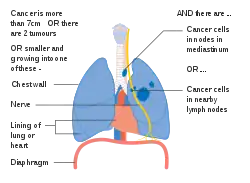

Stage IIIA lung cancer

Stage IIIA lung cancer -

Stage IIIA lung cancer, if there is one feature from the list on each side

Stage IIIA lung cancer, if there is one feature from the list on each side -

Stage IIIA lung cancer

Stage IIIA lung cancer -